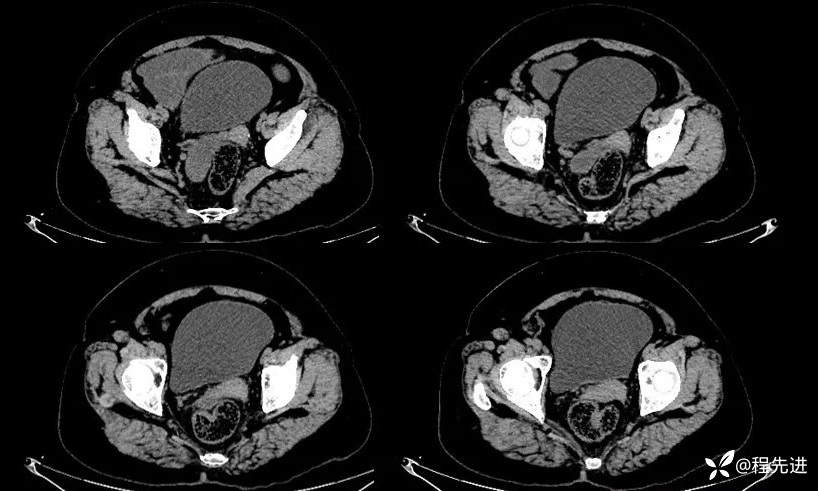

动脉期: